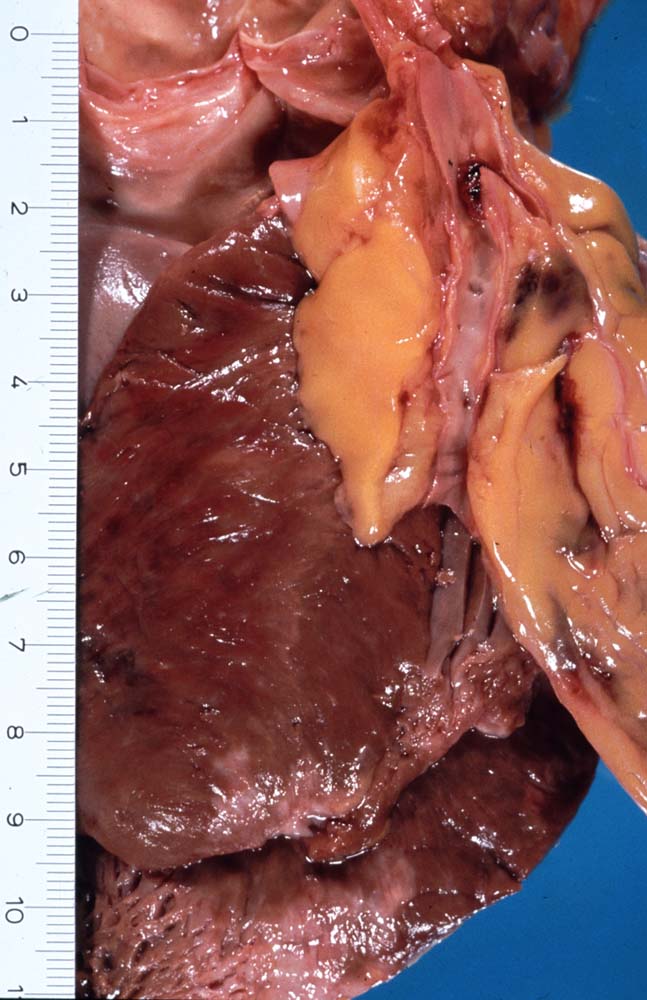

Makroskopisch sind Thromben am besten auf Querschnitten in 3 bis 5mm Abständen durch die Koronargefässe darstellbar. Thromben, die zum Tod des Patienten geführt haben, erkennt man meist makroskopisch. Mikroskopisch findet sich ein Kontinuitätsunterbruch in einer entzündlich veränderten fibrösen Deckplatte über einem Atherom. Dadurch gerät der lipidreiche Kern des Atheroms in Kontakt mit dem luminalen Blutstrom und dies führt zur Ausbildung eines Plättchen-Fibrin Thrombus und zur Einblutung in das Atherom. Meist zeigt der Thrombus Zeichen der beginnenden Organisation. Histologisch ist bei einer Ruptur die denudierte Endotheloberfläche von einem luminalen Thrombus bedeckt.

Makroskopie

Befund

Pathologischer Befund